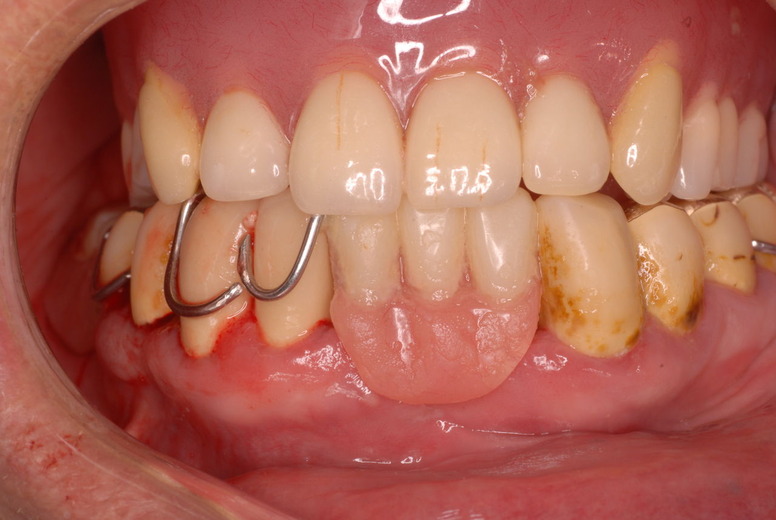

flabby gumと言いまして、骨が溶けてぶよぶよになった歯茎が残るとても入れ歯が吸着したり安定的に食べ物が噛めるような状態でないのです。(歯周病で骨が溶けたとか合わない入れ歯を入れているとなりやすい。)

そしてその部分が擦れて痛む為食事もできないのです。それ以上に驚いたのは、歯を磨いたり歯周病の治療の話を聞いたことがないという事実です。

下の歯は数本存在しますが、全て虫歯と歯周病に犯されていました。

触るとぶよぶよしていて強く押すと痛みがあります。

食べカスまみれで歯周病に罹患しています。